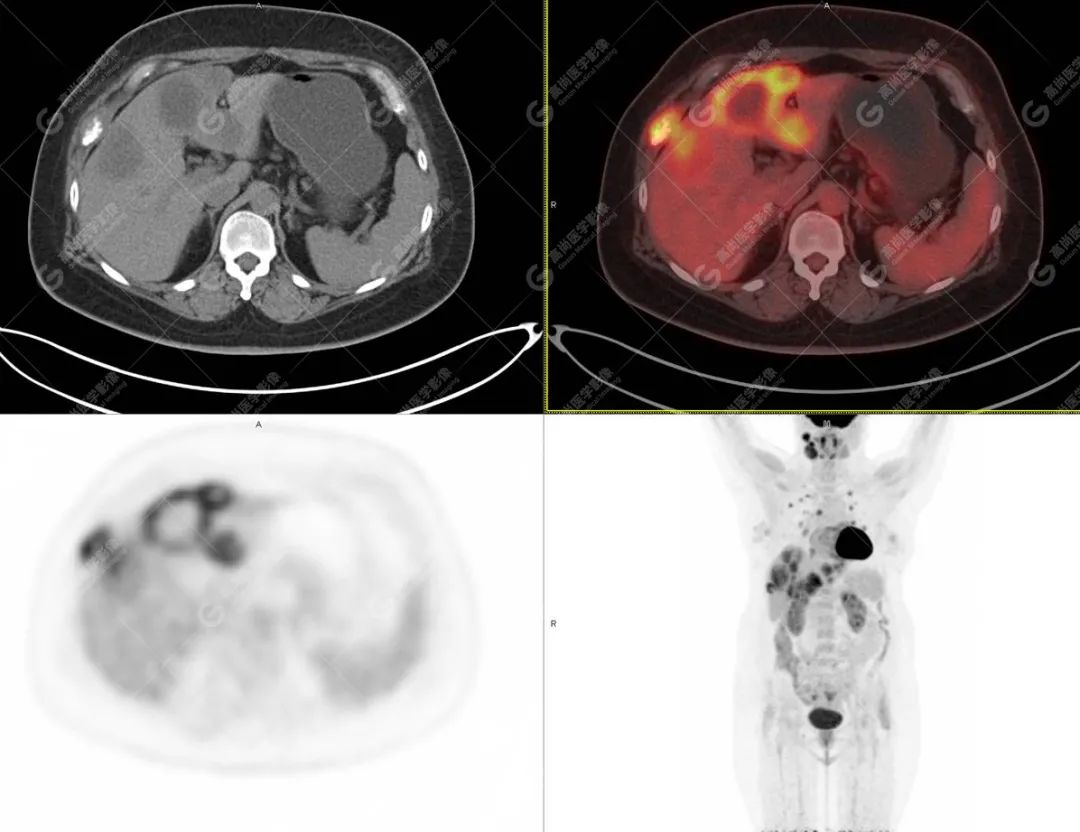

影像诊断:1. 结合病史,右颈部神经鞘瘤(低度恶性)术后改变,右侧颈部稍低密度及等密度结节,代谢异常增高,考虑为肿瘤复发并右颈部淋巴结转移,建议活检。 2. 双侧肺门及纵隔(4R 区)多发肿大淋巴结,代谢异常增高,考虑为转移。 3. 双肺多发大小不等实性结节,部分代谢增高,考虑为转移。 4. 肝脏多发低密度结节及肿块,代谢异常增高,考虑为转移。 5. 右侧第 8 前肋骨骨质破坏,代谢异常增高,考虑为转移。